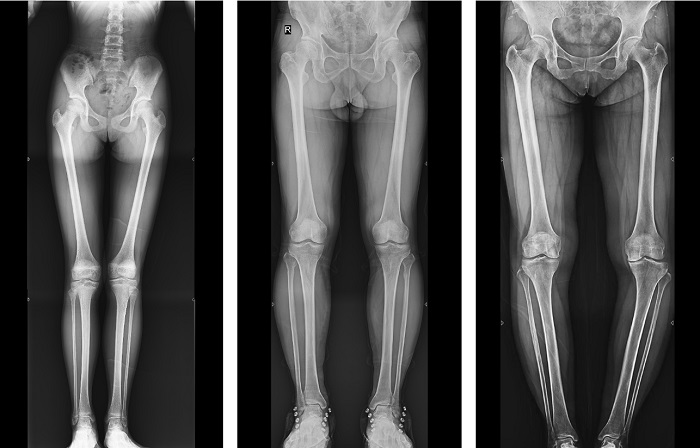

動態(tài)DR全景拼接功能突破平板尺寸長度限制,可進行立臥位攝影,對脊柱、下肢及下肢靜脈造影進行分段攝片,然后對分段圖像進行拼接,在一幅X光圖像上完整顯示全脊柱或下肢整體形態(tài),獲得全脊柱或全下肢圖像,有效解決了傳統(tǒng)X光片不能一次成像問題,通過直觀顯示脊柱和下肢的整體解剖形態(tài)及側(cè)凸部位,為臨床治療提供重要參考依據(jù)。

▲全下肢DR影像

普利德多功能動態(tài)DR進行全脊柱全下肢圖像拼接時,影像密度均勻、清晰、接緣處過渡自然,圖像質(zhì)量高,完全能滿足臨床觀察、診斷及測量要求。拍片過程也更加方便快捷,使患者得到快速診斷,及時治療,為臨床醫(yī)生和患者帶來更大的便利,大大助力醫(yī)院醫(yī)療服務(wù)能力的提升!